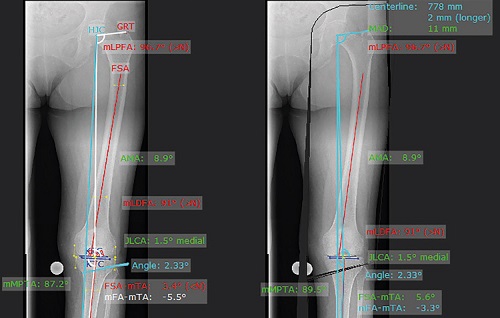

3.Cắt xương theo phương pháp Dror Paley

Phần mềm có thể phân tích xác định loại, số lượng, kích thước và vị trí của u xương. Khi việc điều chỉnh hoàn tất, tất cả các trục chịu trọng lượng cơ học liên quan đến khớp và các tiếp tuyến của khớp phải nằm trong phạm vi bình thường.

Phần mềm mediCAD hiển thị tất cả các kết quả trước và sau phẫu thuật,giúp bác sĩ các hình ảnh trực quan khi lên kế hoạch phẫu thuật. Mô-đun “Cắt xương mở rộng” tính toán được sự sai lệch theo phương pháp của Giáo sư Dror Paley.

Các nguyên tắc toán học của Giáo sư Dror Paley, Giáo sư Tiến sĩ J. Pfeil và Giáo sư Tiến sĩ B. Gladbach.

- Phân tích tình hình trước mổ

- Xác định CORA / NCORA, u xương đơn lẻ hay đa u

- Mô phỏng kết quả trước và sau phẫu thuật.

- Tính toán tự động các góc tối ưu.

- Xác định khối chóp và góc biến dạng thực tế từ các hình chiếu AP và sagittal.

- Đánh giá và lựa chọn cách điều chỉnh lệch trục bằng tay hoặc tự động.